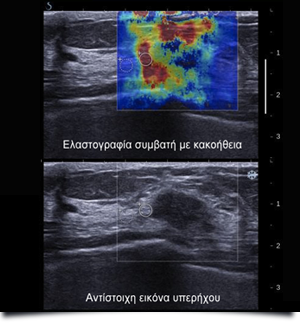

Η ελαστογραφία είναι μια πιο εξελιγμενη μορφή υπερήχων με τη βασική αρχή ότι, εξασκώντας πίεση άνωθεν της βλάβης, μπορεί να μετρηθεί η ελαστικότητα της σε σχέση με παρακείμενο φυσιολογικό ιστό και έτσι μπορεί ο ειδικός ιατρός να χαρακτηρίσει μια βλάβη κακοήθεια ή όχι.

Το απλό τρισδιάστατο υπερηχογράφημα δίνει ικανές πληροφορίες για τη συμπαγή ή κυστική μορφολογία της βλάβης, την αιμάτωσή της και τα όριά της, εάν είναι δηλαδή σαφή, πράγμα που συνήθως αντιστοιχεί σε καλοήθεια, ή ασαφή, που αντιστοιχεί τις περισσότερες φορές σε κακοήθεια. Υπάρχουν όμως και βλάβες, οι οποίες δεν μπορούν να χαρακτηριστούν με σαφήνεια από τον ακτινολόγο και εδώ είναι πολύ σημαντική η χρήση της ελαστογραφίας.